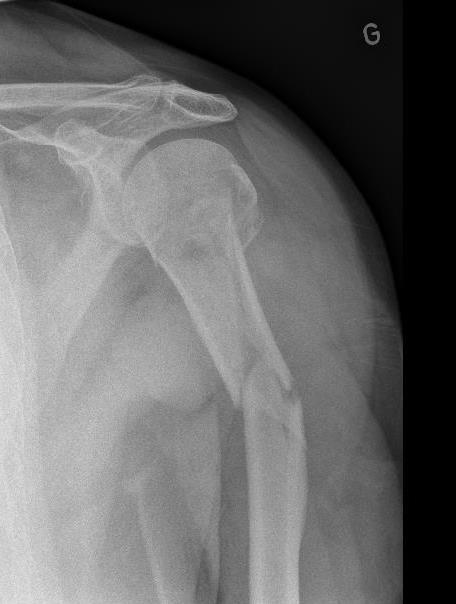

Malgré la regrettable fracture du cuisinier mardi matin 1er janvier, une cuisinière remplaçante s'est proposée et a su ravir les estomacs de tous nos gloutons, affamés par les journées de ski. Le cuisinier est rentré chez lui après une solide opération et il se remet dès à présent de ce malencontreux accident, survenu, même pas sur les pistes, mais devant le chalet, sur une plaque de glace particulièrement glissante !